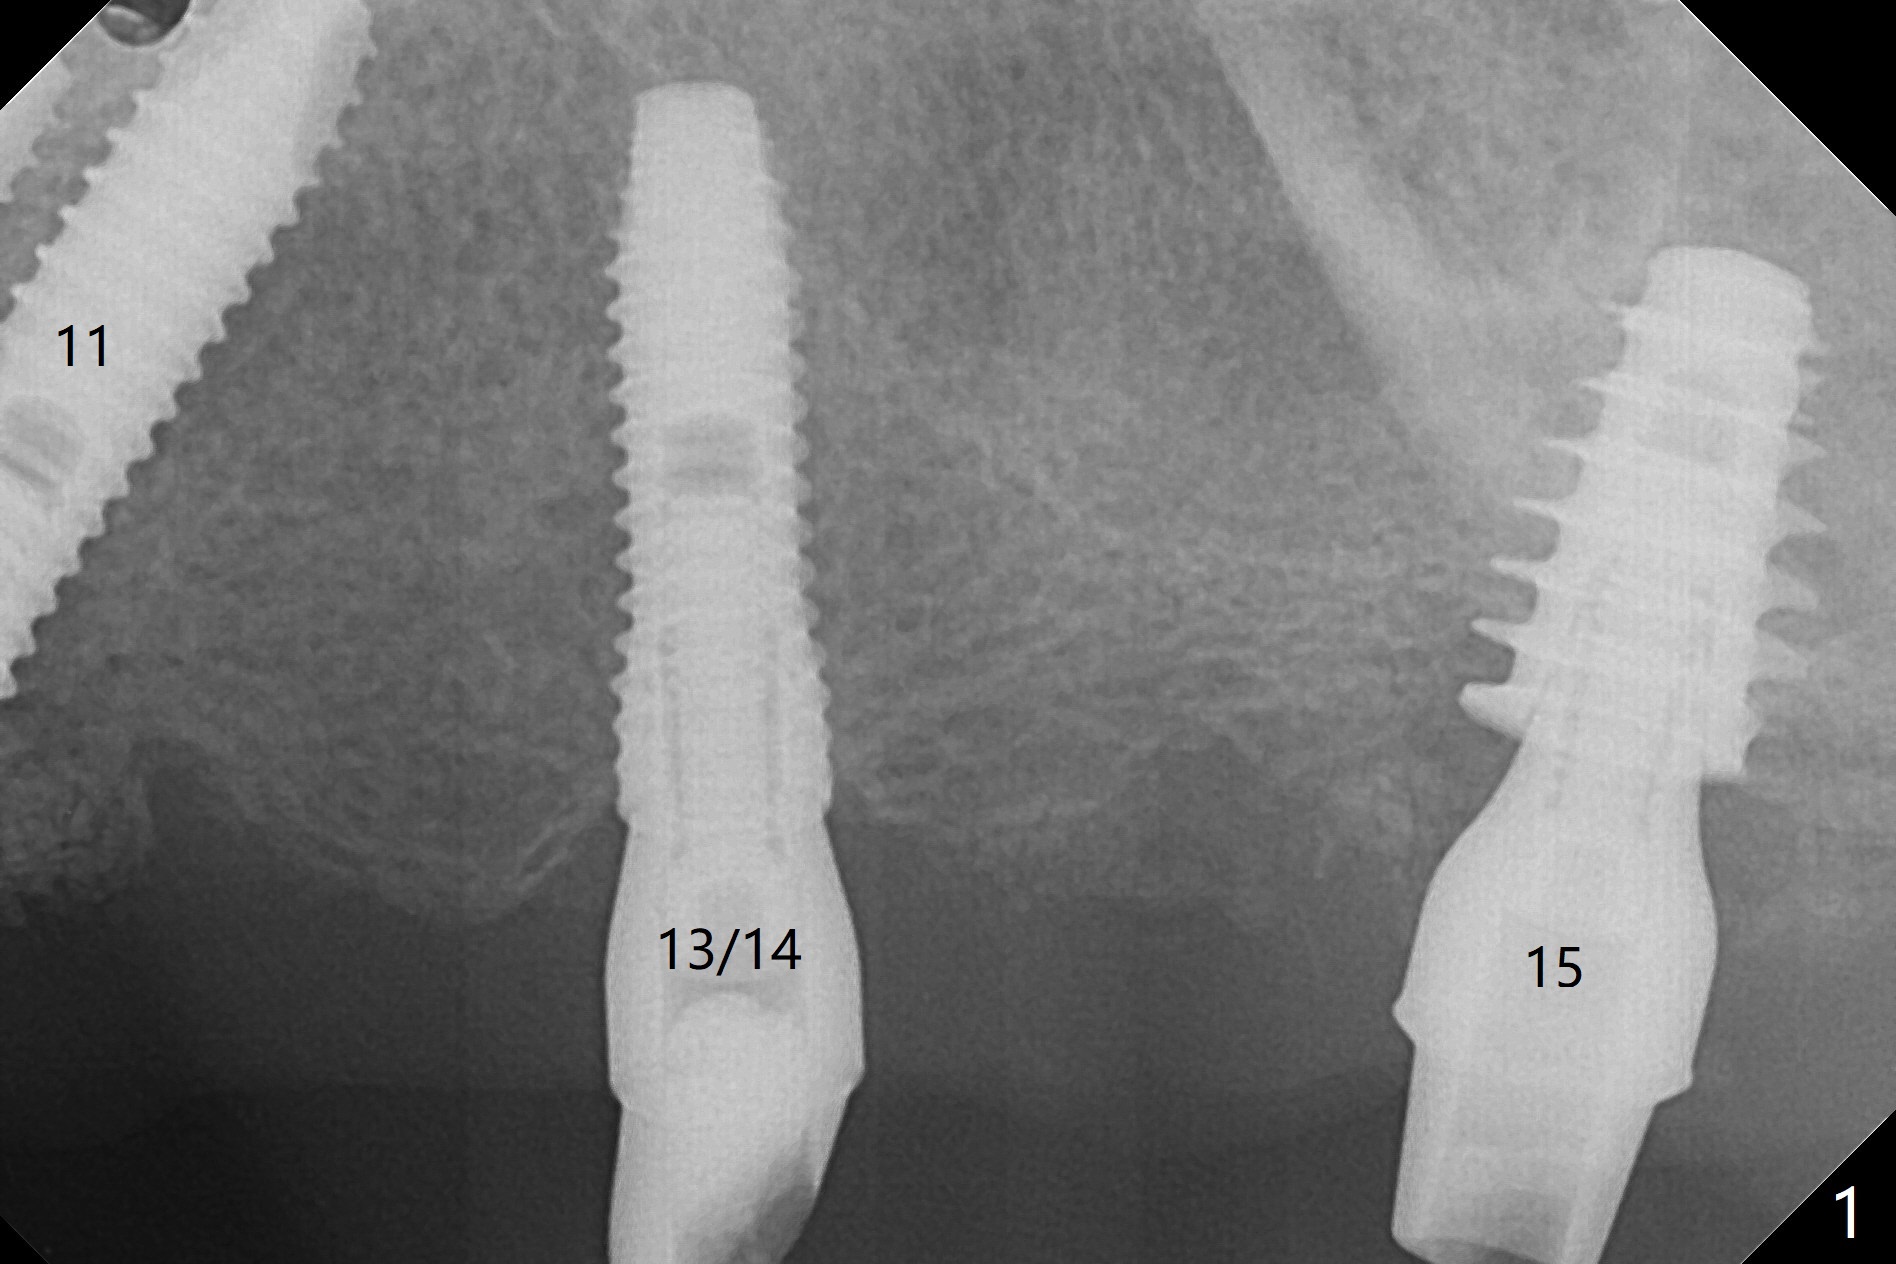

A 48-year-old man returns to clinic with fractured FPD 1 year 5 months post cementation (temp bond, Fig.1,7). It appears necessary to add an implant at #13 site (Fig.2). The narrow ridge is reduced to start an osteotomy (Fig.3 *). After change in osteotomy position and trajectory (Fig.4), a 3x10(4) mm 1-piece implant is placed (Fig.5). With deeper placement of the implant (Fig.6 arrow), cortical bone graft is placed (*).